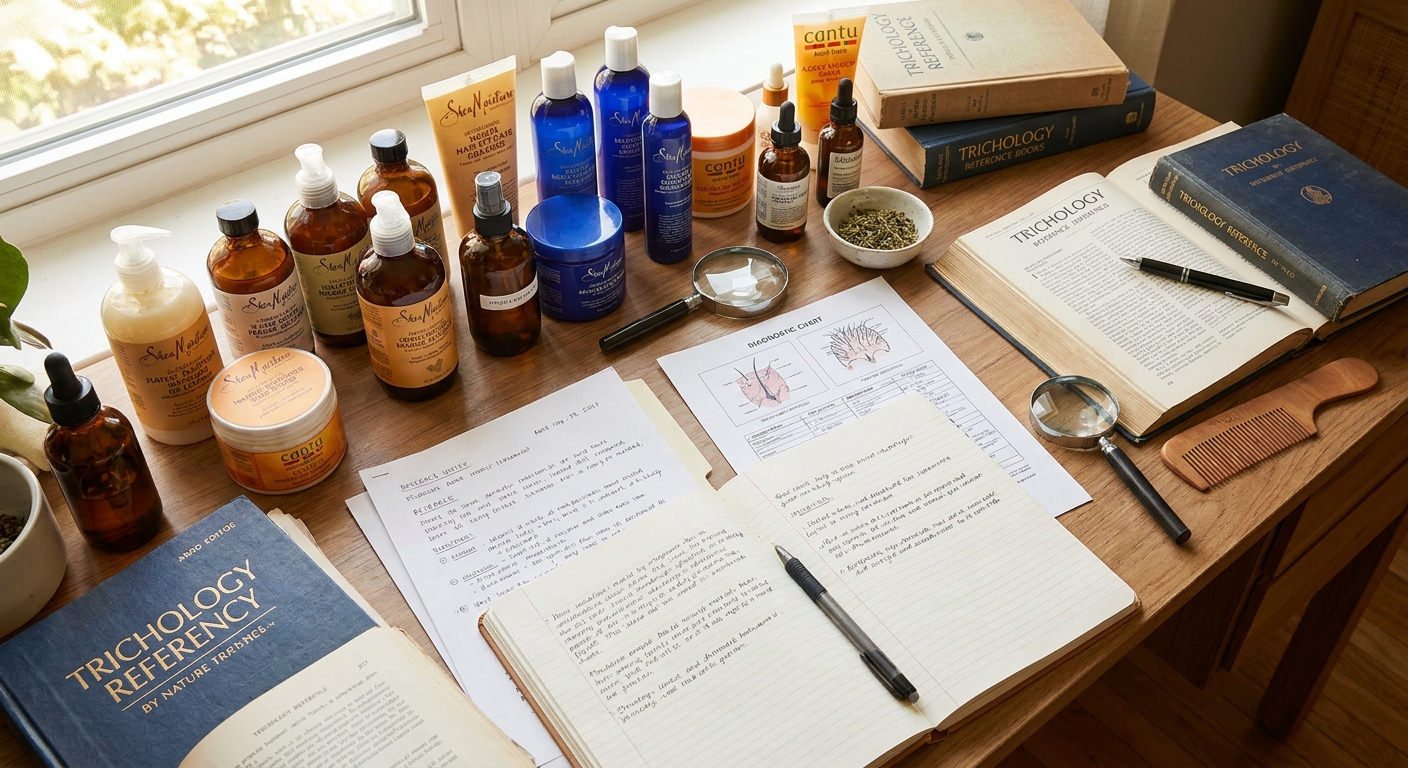

Trychologia to nie stylizacja — to medyczne podejście do zdrowia włosów. Badanie trichoskopowe, szczegółowy wywiad, indywidualny plan terapii dopasowany do Twojego organizmu i budżetu.

Justyna Trela, specjalistka trychologii w Suchym Lesie koło Poznania. Jeśli włosy wypadają, skóra głowy swędzi, a kolejne szampony nie pomagają — zaczynamy od diagnozy, nie od zgadywania.